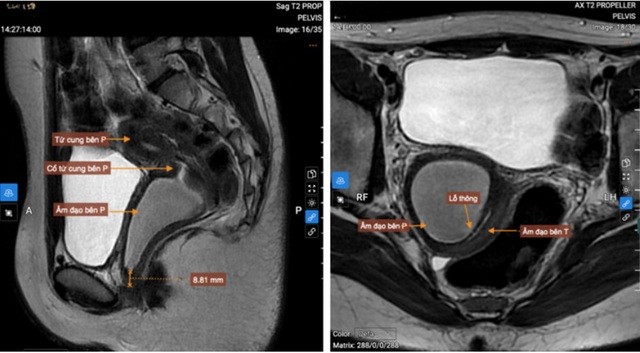

Hình ảnh trên MRI cho thấy 2 sừng tử cung, 2 cổ tử cung riêng biệt, vách ngăn âm đạo. Ảnh: BVCC

MRI vùng chậu ghi nhận hình ảnh tử cung đôi hoàn toàn với hai sừng tử cung, hai cổ tử cung riêng biệt, kèm theo vách ngăn âm đạo. Âm đạo bên phải bị ứ dịch, kích thước khoảng 75 x 40 mm; âm đạo bên trái xẹp, nghi ngờ có lỗ thông nhỏ, vị trí tắc cách tiền đình âm đạo khoảng 9 mm.